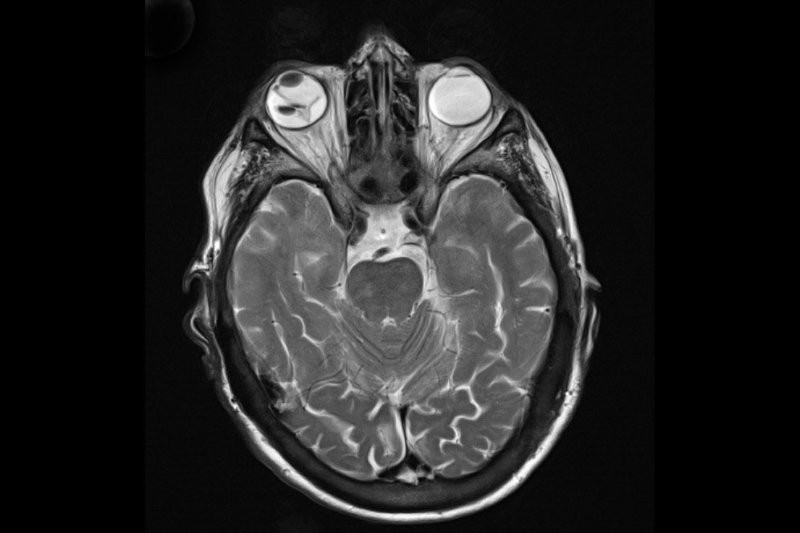

MRI showing retinal detachment. Credit: International Emergency Medicine Education Project